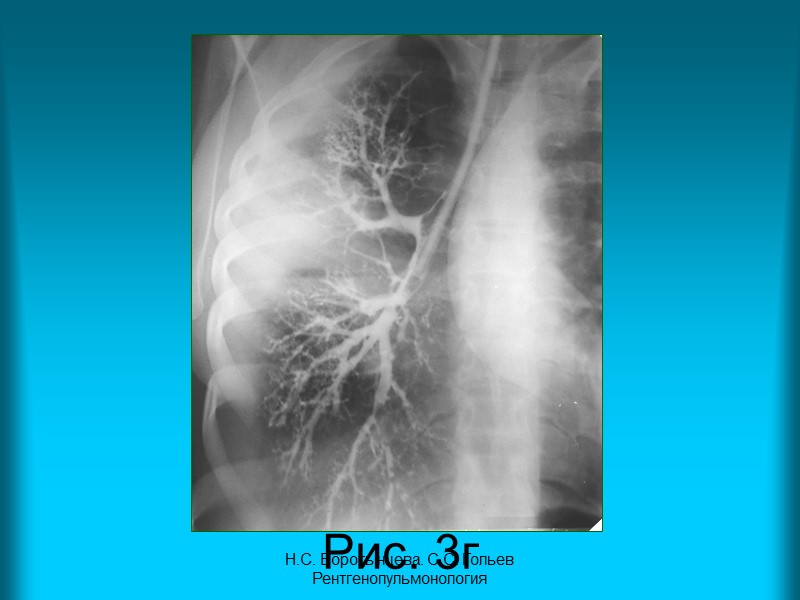

Н.С. Воротынцева. С.С. Гольев Рентгенопульмонология Рис. 3в., Рис.3г. Контрастное исследование бронхиального дерева правого легкого в прямой проекции (бронхография). Определяется сужение и неравномерное заполнение контрастным веществом сегментарного и субсегментарных бронхов третьего сегмента верхней доли правого легкого. Бронхи средней доли правого легкого проходимы, веточки их сближены, но не деформированы.

Н.С. Воротынцева. С.С. Гольев Рентгенопульмонология Рис. 3г